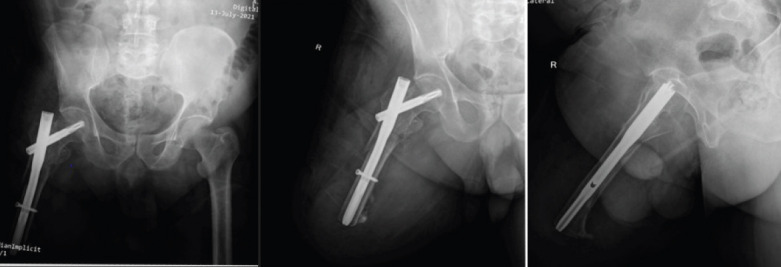

Case report: This report presents the case of an elderly male with a right above-knee amputation who sustained an ipsilateral IT fracture. He had undergone amputation 3 years prior and was mobilizing independently with a prosthetic limb. The current injury occurred due to the rollover of a four-wheeler in which he was traveling. A proximally sized femoral nail was selected for fracture fixation, with the goal of internal splinting across the entire residual femoral length. Postoperatively, the patient resumed use of his previous prosthesis without difficulty.